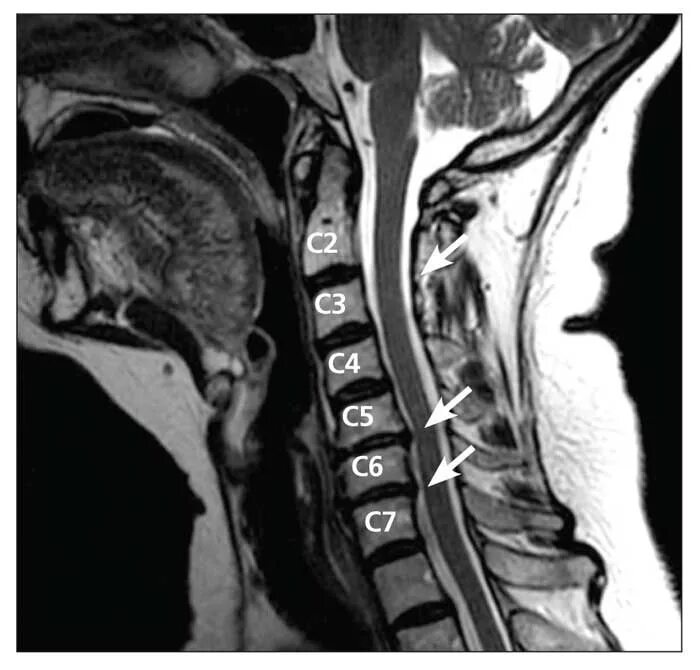

Грыжа диска мрт